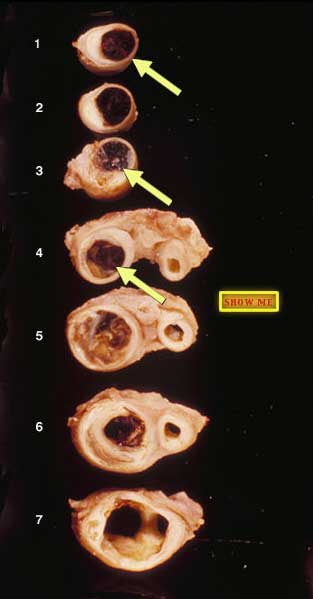

In Section 3, can you find the stringy reddish-brown thrombus that further occludes the lumen? You can also see this in Sections 1 and 4.

Can you see elongated unstained crystal-like profiles?